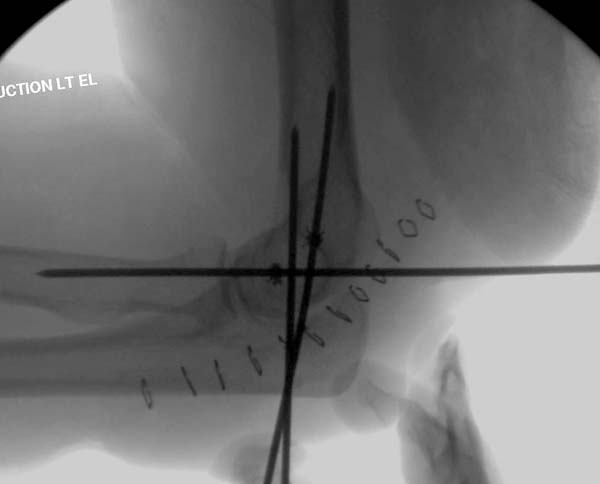

В общем, я хотел сообщить об алгоритме, который применяем у себя. Еще в 1998 году мой партнер по работе Kathy Kramer (скоропостижно скончалась, в ОТА под ее именем имеется грант) написала про наш опыт лечения трансартикулярной фиксацией в 29 случаев вывиха. Кстати, вспомнил прошлогодний спор коллег на Форуме, где площадь повреждения хряща спицами измеряли в мм2. Конечно, такая защита хряща радует, но при игнорированных неделями вывихах? Из-за критики повреждения хряща не позволили опубликовать статью.

Несмотря на отрицательный отзыв, некоторые нестабильные вывихи лечим трансартикулярным методом. Тонкие спицы ломаются и имеют риск внутрисуставной инфекции. Винты 3.5 мм не выдерживают, а более толстые каннюлированные винты неплохо проявили себя. Неосторожность при установке приводила к поломке тонких guide wire внутри сустава. Лучшие кортикальные в 4.5 мм и гипс на три недели. Винт удаляется, затем разработка сустава.

Иногда гипс не гарантировал стабильность и винт внутри гипса ломался. Удаление сломанного винта облегчаем, оставляя на пару мм длиннее с наружной стороны, Т.е винт через олекранон над наружный мыщелок, и никогда в трубку диафиза! Из малого разреза кончик сломанного винта удаляется без проблем.

В заключение: результат применения трансартикулярной фиксации (более 20 лет) в сравнении со сложными реконструктивными операциями показывает лучшую амплитуду движений! Возможно, у коллег имеются другие варианты, а мы без привлечения больших затрат решаем проблему.

Для примера здесь случай начатый в другом центре, а потом переправленный к нам.

Снимки: 1-2 вывих, 4-5 вторичное смещение в гипсе, реконструкция латеральной связки и капсулы 13-14, повторный вывих после реконструкции, перевод в наш центр; 18-21 временная фиксация, 22-25 трансартикулярная фиксация и нестабильная головка фиксирована спицами, 29-30 амбулаторно, 32-33 после удаления винта и спиц...